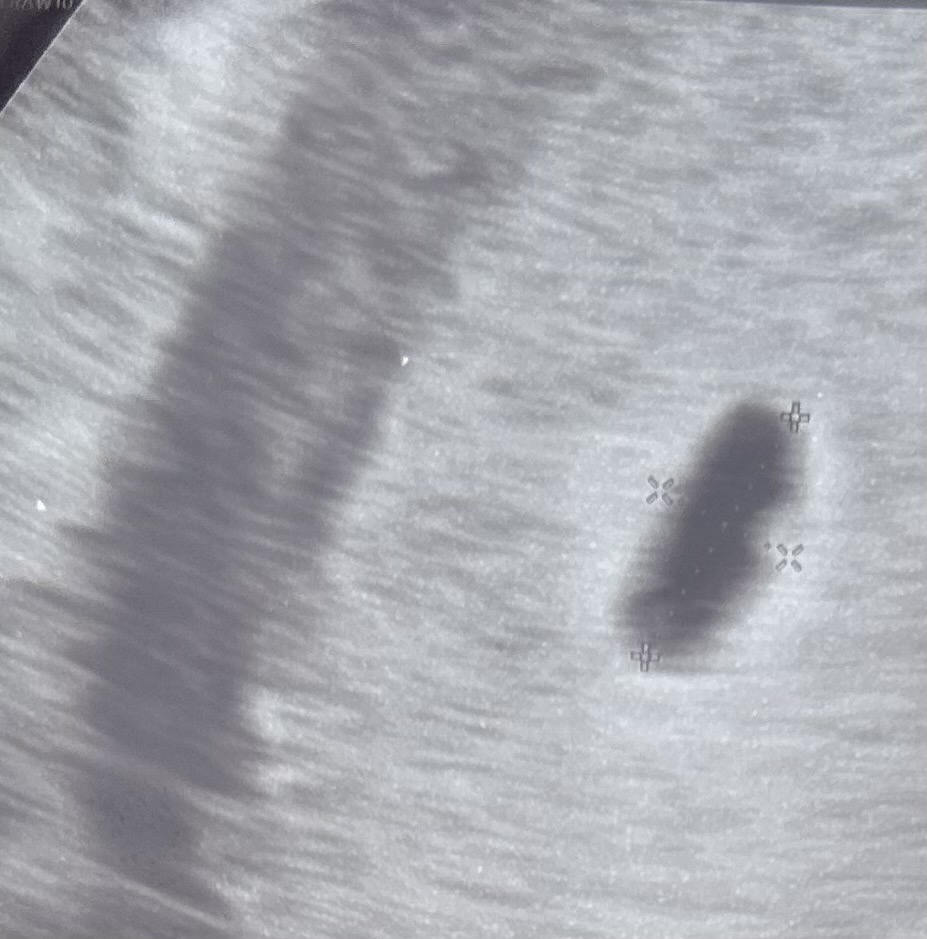

아기집 모양이 원래 이런가요..?

오늘 5주2일차로 다행히 아기집을 봤는데 모양이 약간 조금 찌그러진거 같아서요ㅠㅠ이상이 있고 이런건 아니죠..? 난황이랑 심장소리 들으러 2주 후에 오라고는 하셨습니다..첫 임신이라 걱정이 많네요ㅠㅠ

초음파 보는 각도에 따라 다르게 보이기도 해요 표면이 매끄러우니 괜찮은것같아여

각도에 따라 모양이 달라지기도 해요

사람마다 모양이 다 다르긴한데요~ 피고임 없음 괜찮아요~ 난황도 생기려고 아래 볼록하게 있네요^^